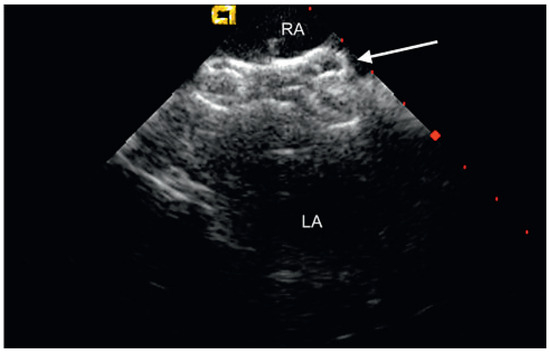

Percutaneous Implantation of an ASD Occluder with Intracardiac Ultrasound

by Frank Enseleit, Oliver Kretschmar and Thomas F. Lüscher

A 52-year-old female was admitted for further evaluation of a continuous heart murmur. Transthoracic echocardiography revealed a secundum type atrial septal defect (ASD II) with a size of 13 × 16 mm and considerable left-to-right shunt (Qp/Qs = 2), as well as elevated [...] Read more.

A 52-year-old female was admitted for further evaluation of a continuous heart murmur. Transthoracic echocardiography revealed a secundum type atrial septal defect (ASD II) with a size of 13 × 16 mm and considerable left-to-right shunt (Qp/Qs = 2), as well as elevated pulmonary artery pressure (RV/RA pressure gradient = 38 mm Hg) [...] Full article